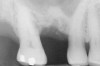

Once it is determined that the twist drill (2.1-mm diameter) is within 1 mm of the sinus floor, the second drill (2.8-mm diameter) and third drill (3.5-mm diameter), if desired, are used to penetrate to within 1 mm of the sinus floor (Figure 3). The amount of osteotomy widening is dependent upon tactilely perceived bone quality.

Figure 3  The osteotomy was completed with the 2.1-, 2.8-, and 3.5-mm twist drills without penetrating into the sinus.

Figure 3